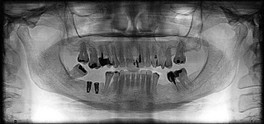

Implantologia

Empleo de los implantes dentales como recurso para la resolución funcional y estética ante la ausencia de piezas dentales.